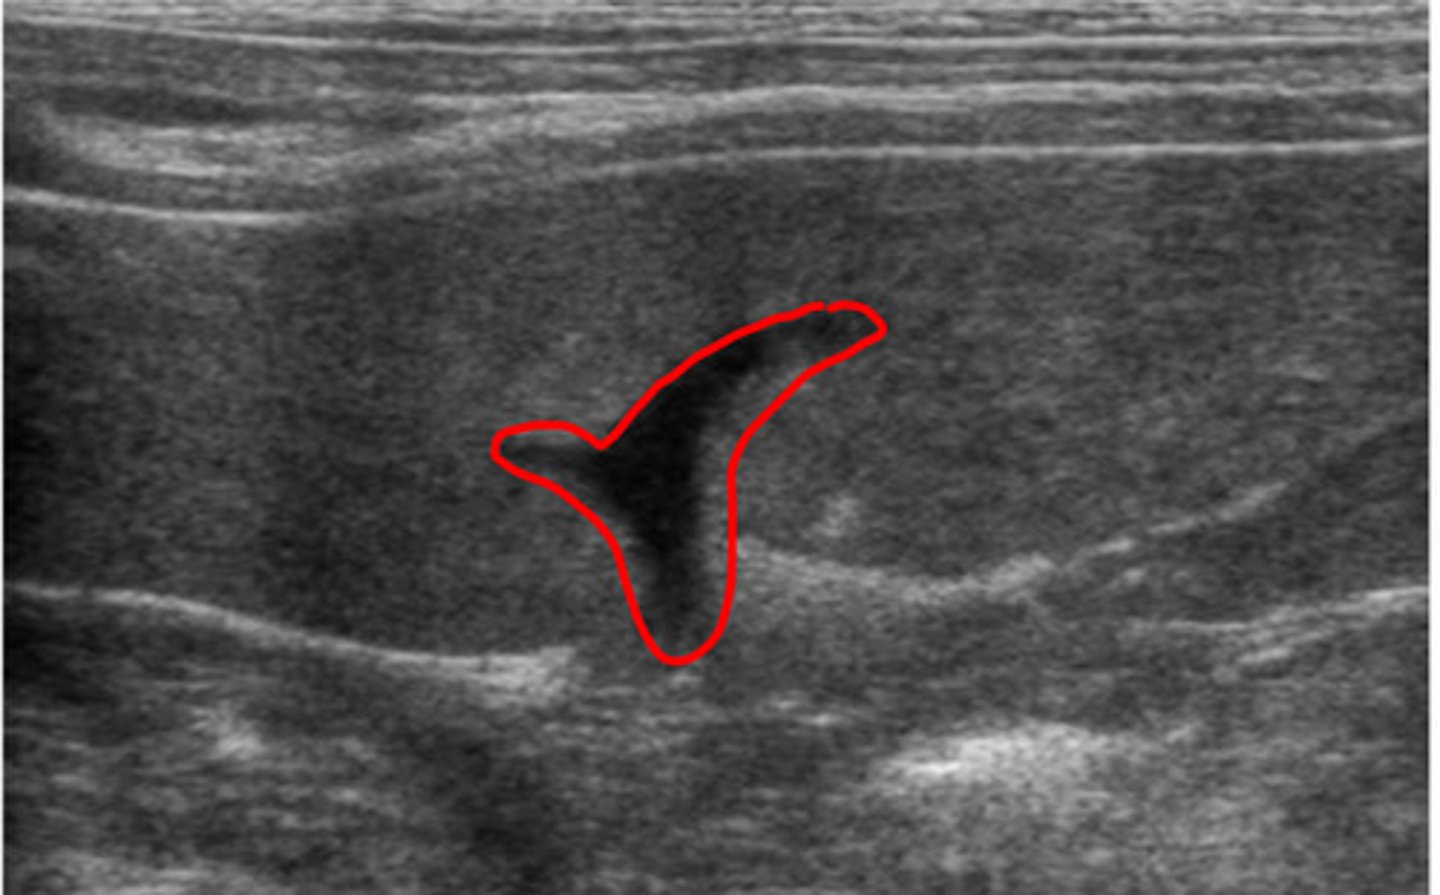

lymph node

ID structure

lymph node

what structure is this?

lymph node

ID structure

lymph node

ID